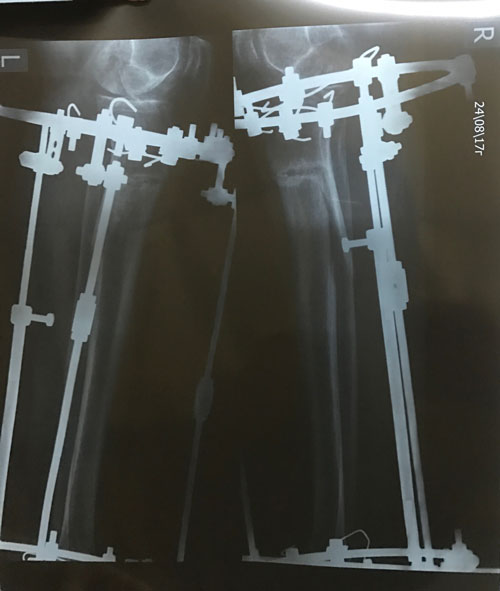

В процессе круток

Рентген и ото ножек в 60 дней.